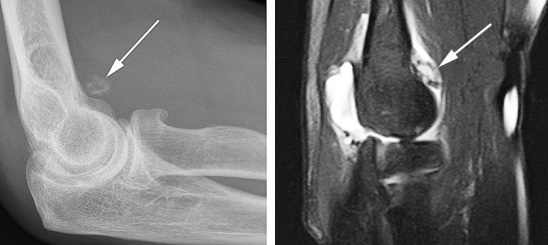

Рентгенограмма (слева) и МРТ локтевого сустава (справа). Суставная мышь (стрелка). Выпот и синовит на Т2-взвешенной МРТ.